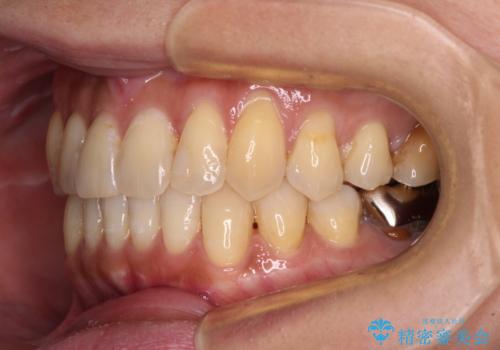

- 前歯のクロスバイトが気になり、インビザラインによる矯正治療を希望して来院された患者様です。

上顎側切歯(上の真ん中から2番目の歯)が舌側転位している場合、インビザラインでは仕上げきれないことが多く、更には無理して動かそうとすると歯髄壊死を起こすリスクが高いと言われています。

インビザラインで歯列を移動する前に、上顎前歯をワイヤー矯正で整え、その後上下歯列をインビザラインにて矯正治療を行うこととしました。

舌側転位している側切歯特有の、切縁の位置が不揃いであったり、根元が内側に引っ込んだ状態であったりという、インビザライン独特の仕上がりになることなく、きれいに整った歯列とすることができました。